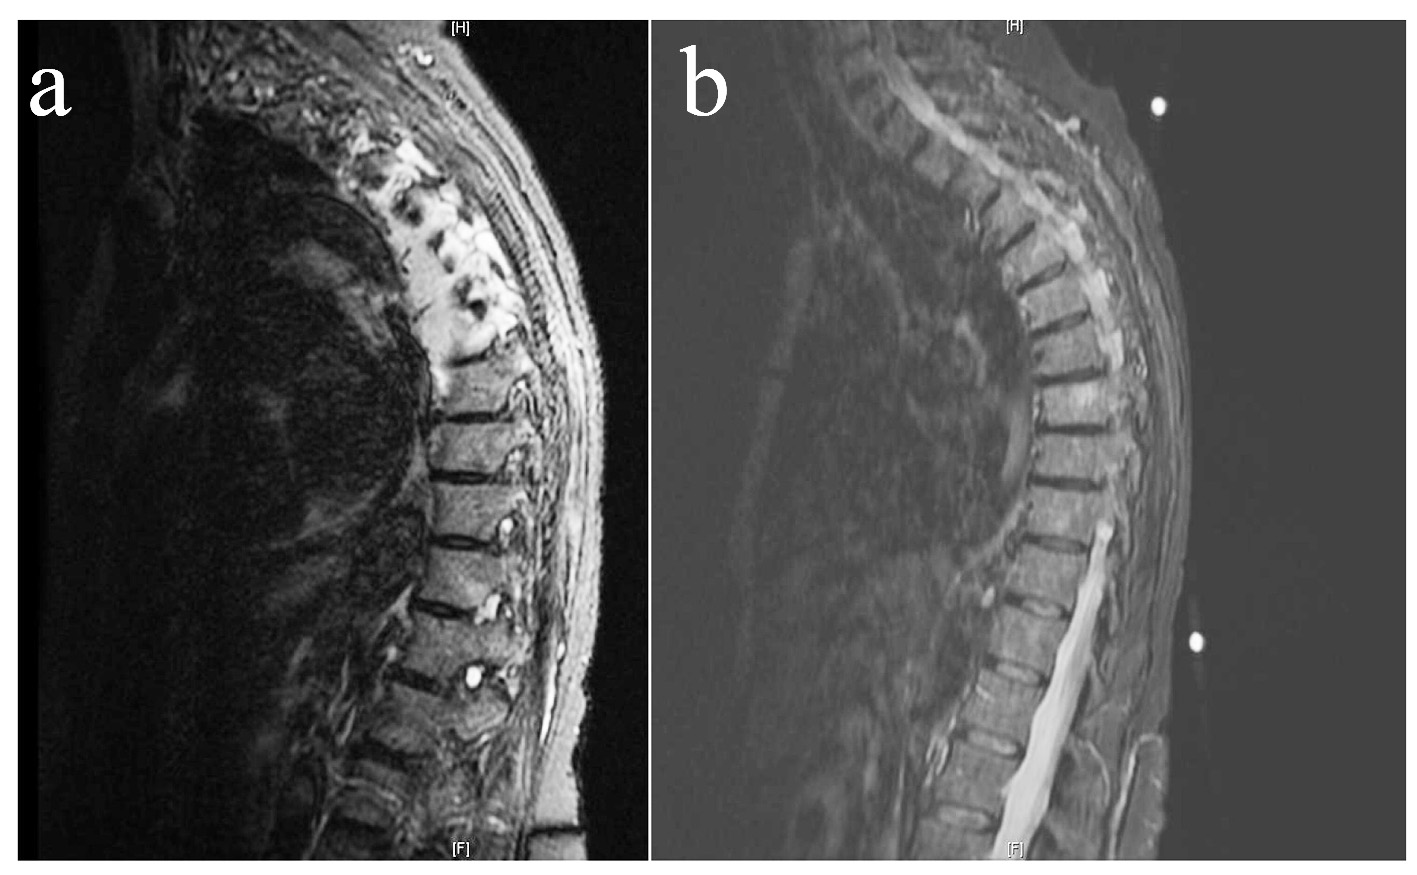

At our hospital, since she was complaining of chest pain, a CT of the chest with contrast, intended to rule out pulmonary embolism, showed bilateral pleural effusions and an increased soft tissue density in the bilateral paraspinal compartment ranging from T4 to T8, which was suspicious for a malignant process. No endobronchial obstruction or pulmonary mass were found. An MRI of the thoracic spine with contrast subsequently revealed multiple foci of bone marrow signal abnormalities suspicious for malignancy, and infiltration of the T4 to T6 vertebral bodies. Extensions into the neural foramens, spinal canal, adjacent ribs, epidural and paraspinal soft tissue were also noted on multiple levels. Additional osseous lesions were found at T7, T8, and T11. Cord compression was pronounced at the level of T4-T5. The tumor had overall progressed and increased in size compared to the prior MRI study done at another facility (Fig. 1a).

![]() Click for large image | Figure 1. Pretreatment (a) and post-treatment (b) T2-weighted MRI showing a near complete resolution of the paraspinal metastatic disease and epidural soft tissue extension, with no evidence of cord compression after three cycles of R-CHOP and intra-thecal methotrexate. |

After discussion with the patient and her family, she was started at our ambulatory oncology clinic on an R-CHOP (rituximab, cyclophosphamide, hydroxydaunorubicin, oncovin, and prednisone) regimen and intra-thecal methotrexate. A follow-up MRI after three cycles of chemotherapy showed an almost complete resolution of the paraspinal metastatic disease and epidural soft tissue extension (Fig. 1b). The patient continues to follow at our clinic 3 months after her diagnosis. She notes that her paresthesia had mostly disappeared. At time of writing, she is being prepared to undergo radiation therapy of the thoracic spine.